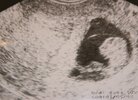

a ja dziewczynki znow jestem ciocia :-):-):-) nowy maluszek urodził sie w sobote ma 57 cm i 3900kg :-):-):-) mały wielkoludek :-) u mnie zaczyna sie gorrrracy okresnajprzyjemniejszy w całym cyklu

![]()